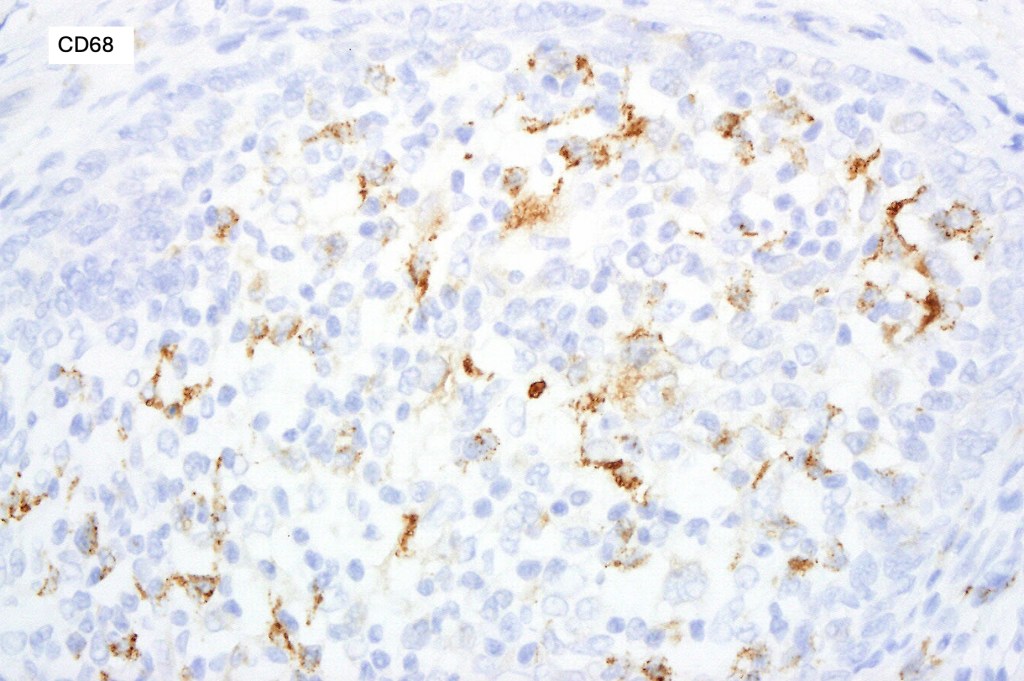

•S100, CD1a +ve Langerhans cells, CD68 +ve histiocytes